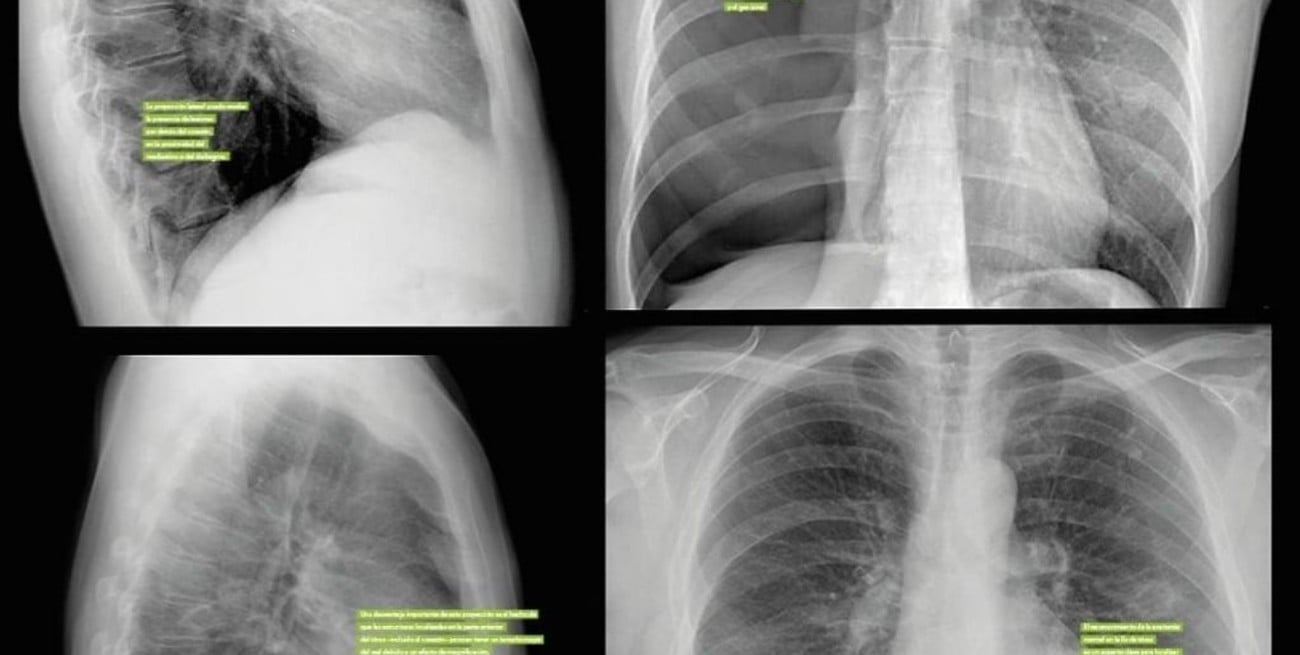

Un egresado de la Universidad Nacional de Córdoba (UNC) diseñó un programa informático que, mediante inteligencia artificial, permite llevar a texto informes de estudios médicos, como radiografías y ecografías, lo que facilita el trabajo de los profesionales de la medicina.